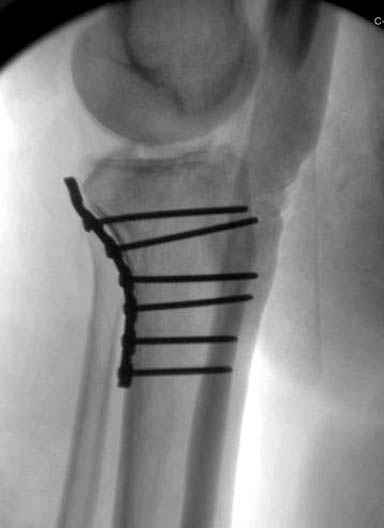

Трудно поверить, что разрекламированная Ортопедическая школа Восточной Украины позволяет такие странные снимки? На прямом снимке сохранен общий контур плато, но не известна судьба импрессии суставной поверхности. На полубоковой?, оставлен без репозиции задне-медиальный отдел, и навряд ли после такой фиксации можно удовлетвориться результатом.

Такая ситуация характерна для многих, когда принимается ошибочное решение, т.е пытаются фиксировать одним имплантом переломы двух мыщелков. Латеральная пластина приемлема только для тех случаев, когда сохраняется интактным медиальный диафизарный кортекс и отсутствует фрагментация на верхушке медиального перелома.

Доступ к медиальной стороне задний или медиальный, через pes или в пространстве между medial gastroc мышцы.